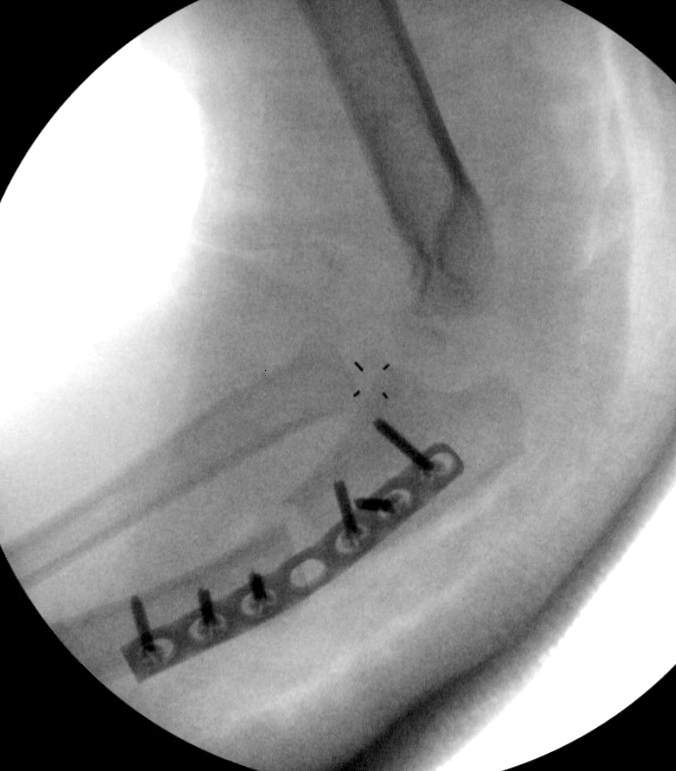

C. May require open approach to radial head with relocation

D. Radial head remains unstable - repair annular ligament or stabilise with strip of triceps fascia

- open reduction radial head

- annular ligament repair +/- reconstruction with strip of triceps fascia